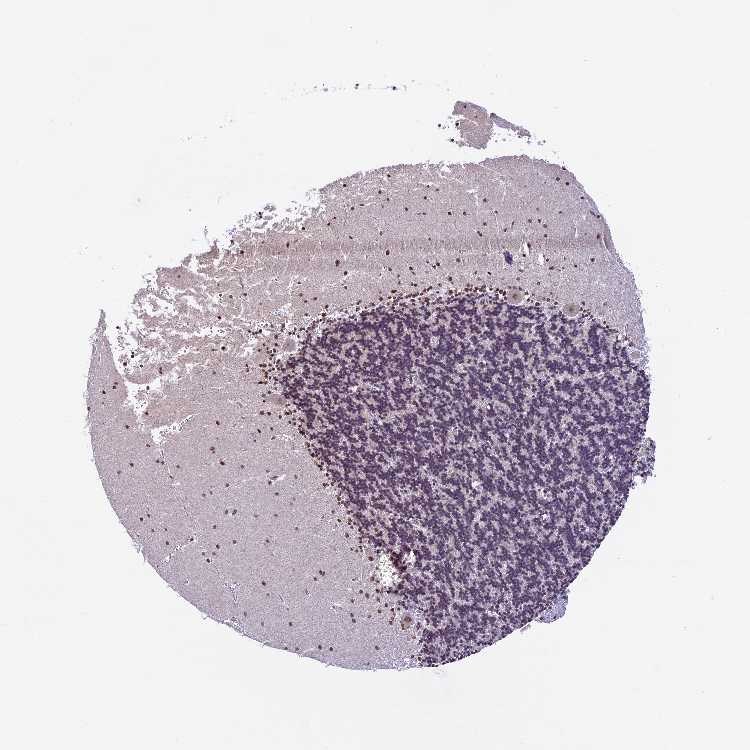

CEREBELLUM - Antibody stainingi

Antibody staining in the annotated cell types in the current human tissue is reported as not detected, low, medium, or high, based on conventional immunohistochemistry profiling in selected tissues. This score is based on the combination of the staining intensity and fraction of stained cells.

Each image is clickable and will lead to virtual microscopy that enables deeper exploration of all samples and also displays staining intensity scores, fraction scores and subcellular localization as well as patient and tissue information for each sample.

Antibody HPA041776

Purkinje cells Medium

Cells in granular layer Not detected

Cells in molecular layer High